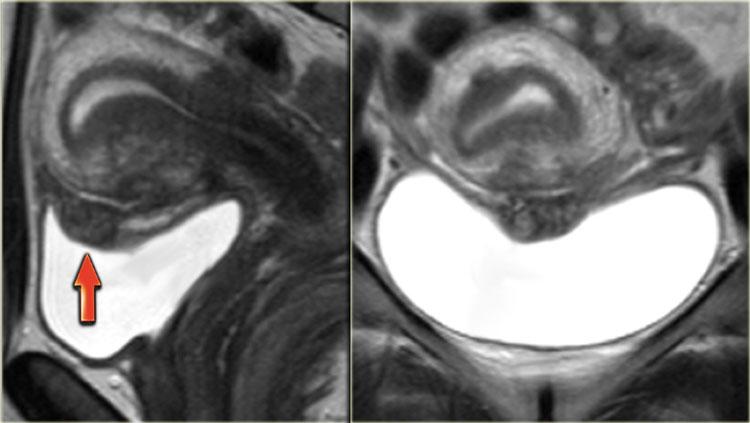

Hình ảnh T2W cho thấy lạc nội mạc tử cung xâm lấn thành bàng quang.

Hình ảnh T2W mặt phẳng đứng dọc cho thấy lạc nội mạc tử cung bàng quang xuyên toàn bộ chiều dày thành với tín hiệu đồng tín hiệu so với cơ và các ổ tăng tín hiệu, gợi ý các tuyến nội mạc tử cung giãn rộng.

Hình ảnh T1W kỹ thuật ức chế mỡ cho thấy các nang nhỏ tăng tín hiệu trong tổn thương do xuất huyết.